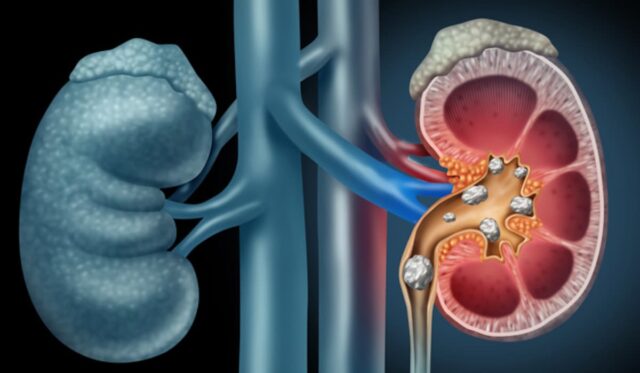

दरअसल, गर्मियों में शरीर लगातार अपने तापमान को नियंत्रित करने में लगा रहता है, और इसके लिए पसीना आना जरूरी प्रक्रिया है। लेकिन जब पसीने के जरिए शरीर से पानी निकलता है और उसकी भरपाई नहीं होती, तो किडनी के पास फिल्टर करने के लिए पर्याप्त तरल नहीं बचता। इस वजह से पेशाब की मात्रा कम हो जाती है।यूरिन ज्यादा गाढ़ा हो जाता है। साथ ही इसमें कैल्शियम, ऑक्सालेट और यूरिक एसिड जैसे तत्व जमा होने लगते हैं।यही तत्व मिलकर धीरे-धीरे पथरी का रूप ले लेते हैं।

किडनी स्टोन का खतरा उन लोगों में ज्यादा होता है जो कम पानी पीते हैं, जिन्हें पहले पथरी हो चुकी हो या परिवार में इसका इतिहास हो, जो ज्यादा नमक, नॉन-वेज प्रोटीन और ऑक्सालेट वाली चीजें खाते हैं, साथ ही मोटापा, मेटाबॉलिक सिंड्रोम या बार-बार यूरिनरी ट्रैक्ट इन्फेक्शन से जूझ रहे होते हैं।